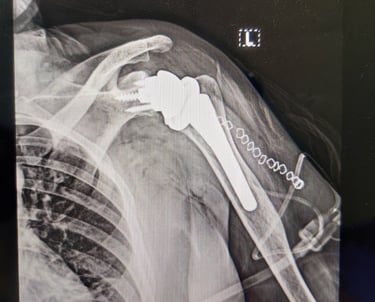

Shoulder replacement surgeries-

Anatomical and Reverse Shoulder replacement

Revision shoulder replacements

Stemless shoulder replacement

Partial Shoulder replacement